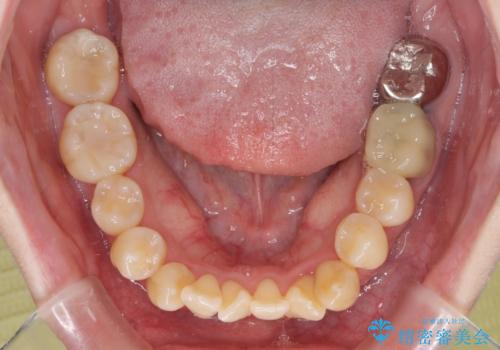

急速拡大装置 狭い骨幅を拡大した上で、顕著なデコボコを改善する抜歯矯正治療

- 前歯のデコボコと唇の閉じにくさを気にして来院された患者様です。

上顎骨よりも下顎骨の幅が広く、更には下顎骨が左側に変位していたため、より良い咬み合わせを達成することを目的として、急速拡大装置を用いて上顎骨を拡大することとしました。

デコボコが強い上に、口元の突出感も気にしていたため、上下左右の小臼歯4本を抜歯して、ワイヤー装置にて矯正治療を行うこととしました。